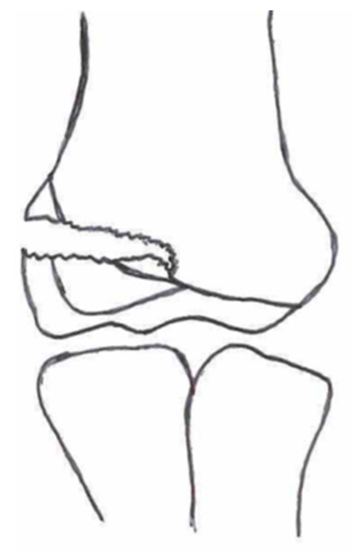

2.3. Classification of Fractures

| Classification | Type 1 (A) | Type 2 (B) | Type 3 (C) | Type 4 | Type 5 |

|---|---|---|---|---|---|

| Milch. [16] | ![]() | ![]() | |||

| Jacobs et al. [21] | ![]() | ![]() | ![]() | ||

| Finnbogason et al. [22] | ![]() | ![]() | ![]() | ||

| Weiss et al. [23] | ![]() | ![]() | ![]() | ||

| Song et al. [4] | ![]() | ![]() | ![]() | ![]() | ![]() |